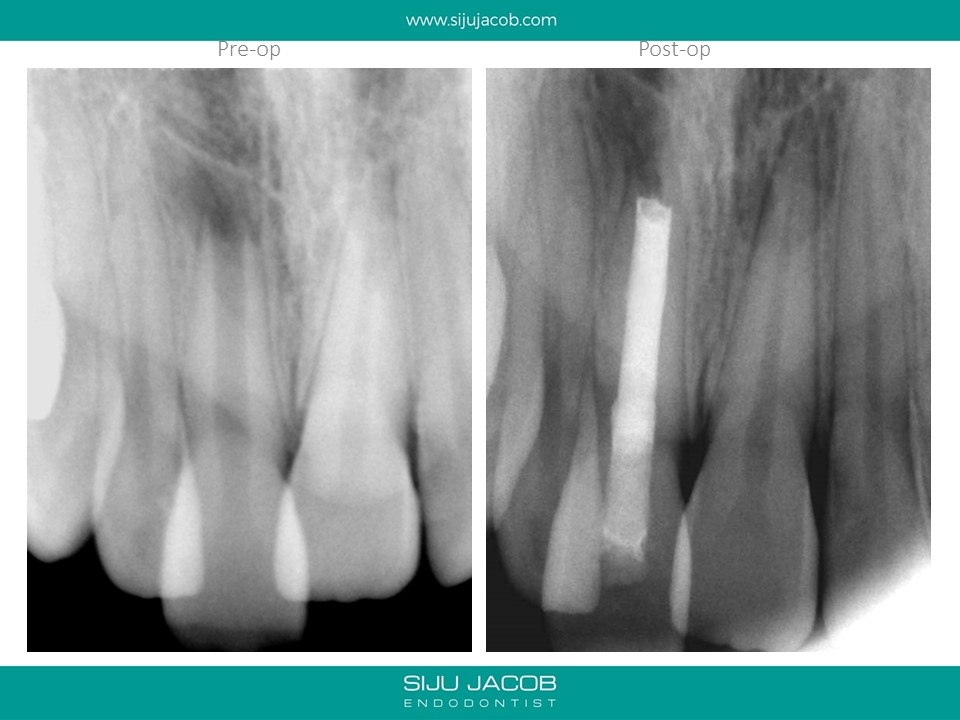

This was one of the first apexification cases i did. I started this case before i purchased a microscope (and I wasn’t using MTA at that time). I packed the canal with a thick Iodoform + Calcium hydroxide (Metapex). By the time the patient came back after a year, I had a microscope and it was fascinating to Microscopically observe the apical barrier that had formed.